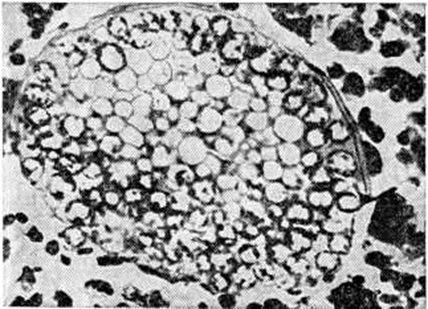

Очаги поражения при североамериканском бластомикозе имеют сходство с таковыми при раке или туберкулёзе, так как подвергаются творожистому некрозу или гнойному расплавлению. При гистологический исследовании обнаруживают очаги некроза с разрастанием грануляционной ткани в их окружности, которая содержит гигантские клетки. PAS реакция выявляет Blastomyces dermatitidis среди клеток инфильтрата или в гигантских клетках (рисунок 2).

Рис. 2.

Микропрепарат лёгкого при североамериканском бластомикозе, вызванном Blastomyces dermatitidis: дрожжевые клетки грибка (указаны стрелками) в цитоплазме гигантских клеток; окраска по Хочкиссу — Мак-Манусу; ×280.